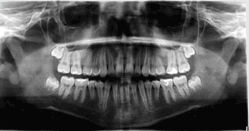

Panoramaticky Rentgen Opg